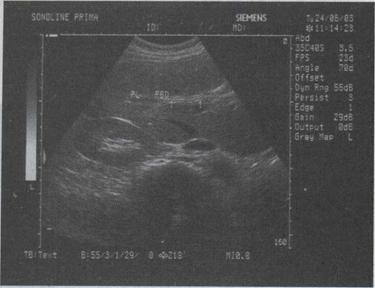

32.女,34岁,上腹疼痛不适数年,加重2天。声像图如图所示。结合超声声像图,诊断为()